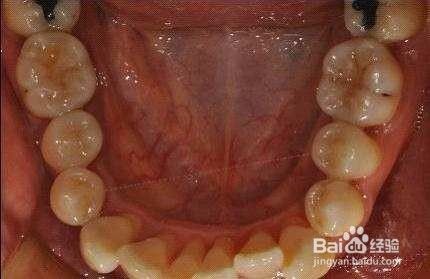

糜烂性扁平苔藓。这个主要表现为口腔黏膜出现网状的白色的条纹、发红、糜烂,有痛感。如果伤口长期不愈合,甚至会有癌变的风险。